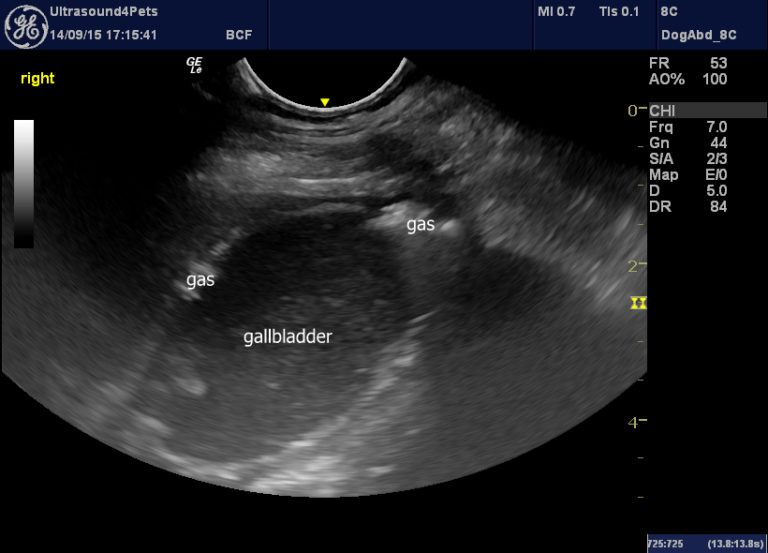

Veterinary Ultrasound Diagnostic Imaging Clinical Images Search Esaote

Veterinary Ultrasound Diagnostic Imaging Clinical Images Search Esaote Dog Gallbladder Sludge One of the most common symptoms of gallbladder sludge is abdominal pain. Web canine gallbladder mucocele (gbm) is characterized by progressive accumulation of tenacious pale yellow to dark green. Web gallbladder sludge, also known as gallbladder mucocoele (gbm), is a condition that affects dogs, specifically their gallbladders. Web gallbladder sludge is a condition that can affect your dog's digestion and. Dog Gallbladder Sludge.